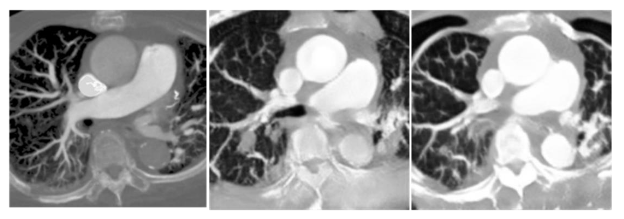

First, we input the original DICOM images for the first training, and found that the CT values of each pixel in the DICOM file were too widely distributed, which caused the model output to fail to focus on the PE features. Since our goal is to detect PE, we try to pass the input images through a HU filter first, and keep the relevant CT values of lungs and blood vessels into the model to enhance the model’s ability to restore PE features. In addition, since CycleGAN is an unsupervised adversarial generative neural network, we believe that if we can add a pre-trained classification network for PE features in its discriminator, it can enhance its ability to restore PE features. In

, we can see that with the addition of the classification network, CycleGAN can focus more on the vascular features and lung regions for reproduction, and the overall image similarity is greatly improved. In each of the image evaluation indexes (

In the generated results in

, we can see that the generated model reproduces the vascular vein as much as possible, but there are still many differences that are visible to the naked eye, and we will discuss how the model is adjusted later. As detailed in